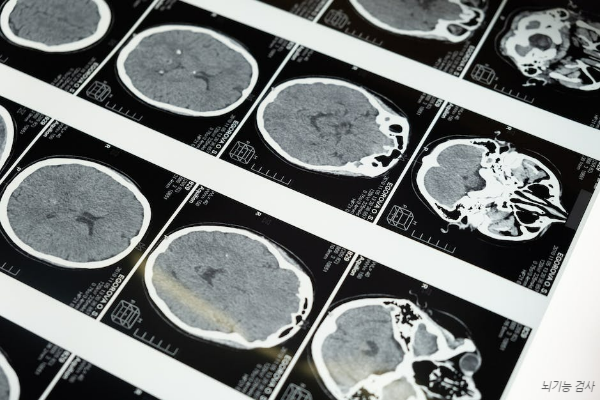

이러한 혈액 공급에 문제가 생겨서 발생하는 뇌혈관 질환에는

대표적으로 뇌출혈, 뇌경색, 뇌동맥류, 지주막출혈 등이 있어요.

흔히 의학계에서 뇌졸중이라고 부르고, 흔히 중풍이라고 불리는 질환입니다.

여기서 뇌혈관이 막히는 경우와 뇌혈관이 터지는 경우로 나누면

전자는 뇌경색이고, 후자는 뇌출혈입니다.

또한, 정기적으로 뇌건강에 대한 검진을 통해 조기발견이 중요하며,